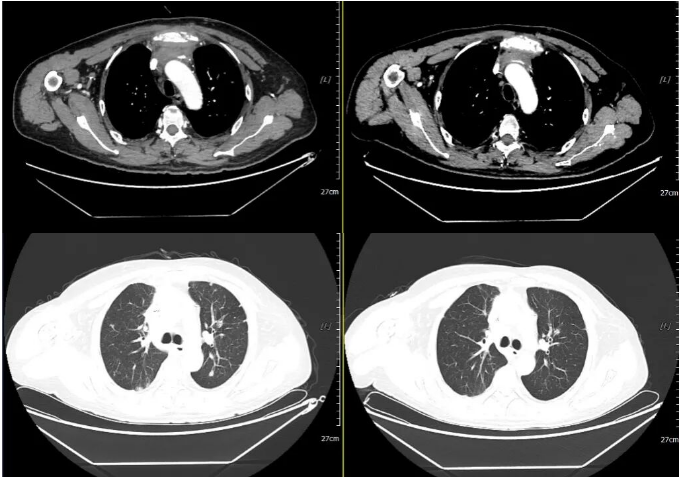

2023-01-30 2023-03-03

2023年1月30日开始口服“马来酸阿法替尼片(自带)40mg 口服 qd”靶向治疗。

2023年3月3日我院复查胸腹盆平扫CT、头颅平扫MR:疗效评估:SD(病情稳定)